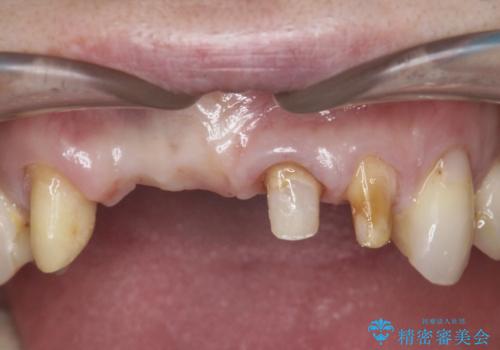

前歯が折れた 前歯部審美セラミックブリッジ治療

- ブリッジの根元が折れ、審美性の改善・治療を求めて来院されました。

保存の難しい歯を抜去しロングブリッジによる補綴を選択しました。

かみ合わせの観点からインプラント治療は難しく、入れ歯も希望されなかったためブリッジによる補綴を選択しました。